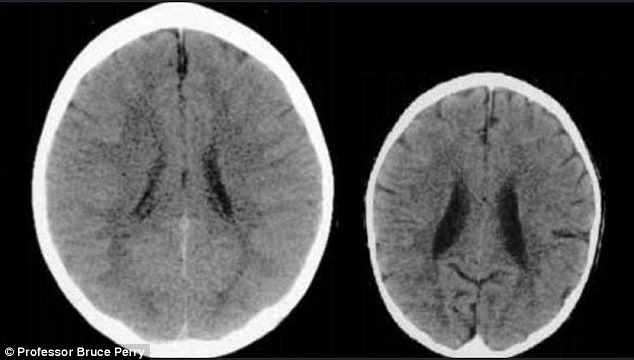

Hình ảnh chụp CT bộ não 2 đứa trẻ cùng độ tuổi. Bên trái là não của trẻ được quan tâm, yêu thương và bên phải là não của trẻ bị bỏ mặc, lạm dụng tinh thần hoặc thể chất (Ảnh minh họa)

Đừng nghĩ rằng yêu chiều bé quá nhiều sẽ làm hỏng bé vì thực tế hoàn toàn ngược lại. Những cái ôm và những nụ hôn thường xuyên sẽ đảm bảo giúp trẻ tạo ra các kết nối thần kinh mạnh mẽ hơn và cải thiện sức khỏe tổng thể của chúng. Một nghiên cứu của các nhà tâm thần và thần kinh học trẻ em tại Đại học Washington ở St Louis đã tìm thấy một mối quan hệ mạnh mẽ giữa tình yêu của cha mẹ và sự phát triển kích thước não bộ của trẻ em.

Trẻ em sống trong môi trường gia đình giàu tình thương yêu có não bộ lớn hơn và phát triển tốt hơn những đứa trẻ khác cùng độ tuổi. Ôm ấp và vuốt ve con thường xuyên cũng giúp giải phóng các hoóc môn quan trọng giúp não bộ của trẻ phát triển. Vì vậy, mẹ hãy ôm bé thật chặt, đặc biệt là khi bé khó khăn khi ngủ lại hay lần đầu tiên bị cảm lạnh.